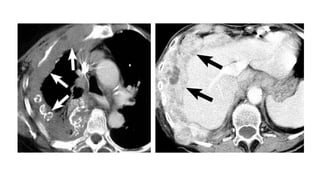

Es necesario la administración de contraste intravenoso para poder valorar el realce de la

pleura y diferenciar el derrame del parénquima pulmonar atelectasiado.

HALLAZGOS TAC

• Engrosamiento nodular pleural o crecimiento tumoral pleural con

morfologia de corteza (Rind-like)

• Derrame pleural unilateral

• Engrosamiento tumoral de las cisuras

• 10-52% Placas pleurales calcificadas

• Pérdida de volumen hemitórax afecto

• Ausencia de reexpasión pulmonar tras toracocentesis evacuadora

Diagnóstico: Es necesario laadministración de contraste intravenoso para poder valorar el realce de la pleura y diferenciar el derrame del parénquima pulmonar atelectasiado. HALLAZGOS TAC • Engrosamiento nodular pleural o crecimiento tumoral pleural con morfologia de corteza (Rind-like) • Derrame pleural unilateral • Engrosamiento tumoral de las cisuras • 10-52% Placas pleurales calcificadas • Pérdida de volumen hemitórax afecto • Ausencia de reexpasión pulmonar tras toracocentesis evacuadora